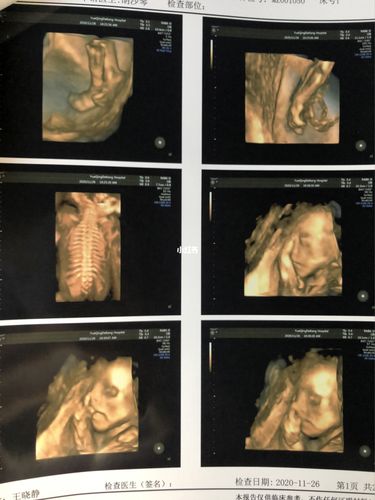

男孩四维图片,四维彩超男孩清晰图

四维彩超男孩清晰图

男孩四维彩超图及数据

男孩四维彩超胎儿图片

四维彩超图片 男孩